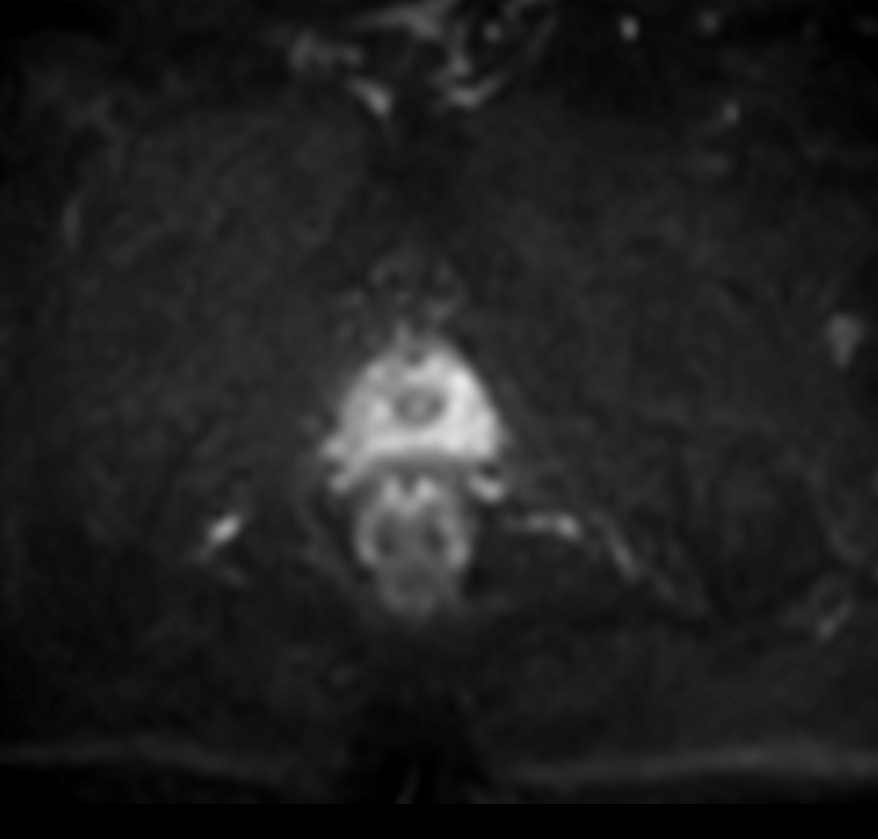

Prostate lesion with fat-free mDIXON XD imaging

Seirei Mikatahara General Hospital, Japan